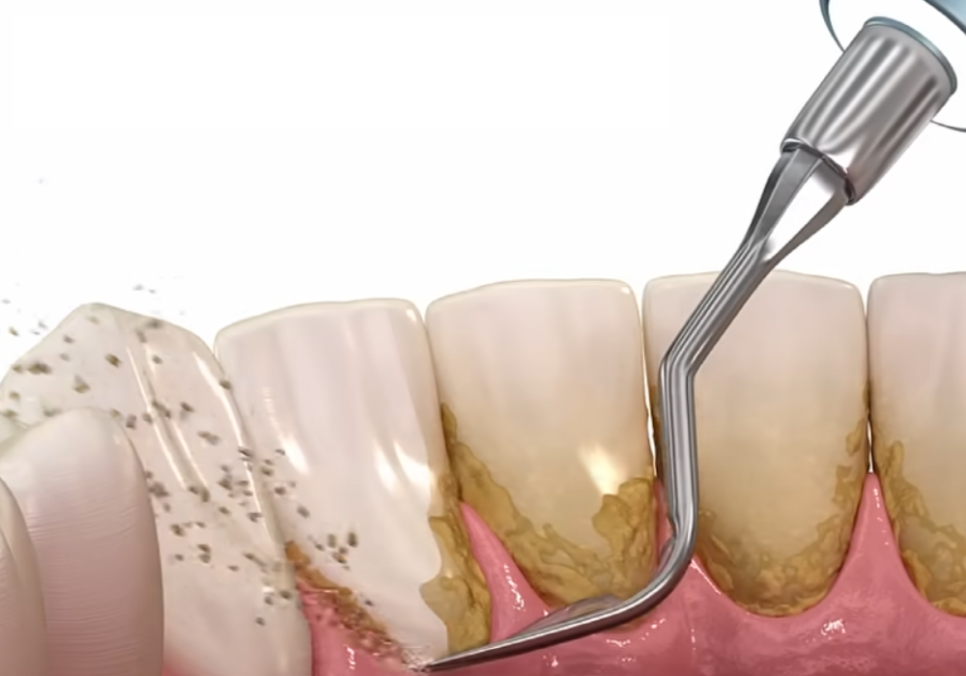

스케일링은 단순히 치아 표면을

깨끗하게 닦아내는 청소가 아니에요.

잇몸 질환의 근본적인 원인인

치석을 제거하는 예방 치료입니다.

치석은 치태(플라그)가

침 속의 무기질과 결합해

돌처럼 딱딱하게 굳은 것인데,,

이건 칫솔질만으로는

절대로!! 떨어지지 않아요.

치석을 제때 제거하지 않으면

그 위로 계속해서 세균이 번식하고,

잇몸에 염증을 일으킵니다.

치은연하치석의 위험성

눈에 보이는 치석보다 더 무서운 것이

바로 잇몸 라인 아래쪽에 숨어있는

'치은연하치석'이에요.

이 치석들은 잇몸 깊숙한 곳에 자리 잡아

점점 잇몸뼈를 녹입니다.

이렇게 잇몸 안쪽까지 파고든 치석은

치아를 지탱하는 힘을 약화시켜

결국 멀쩡해 보이던 치아를 흔들리게 만듭니다.